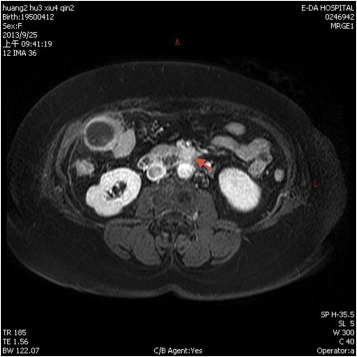

Axial contrast enhanced computed tomography abdomen demonstrated a 1.6-cm ...

Axial contrast enhanced computed tomography abdomen demonstrated a 1.6-cm enhancing mass (arrow) in the uncus of the pancreas.